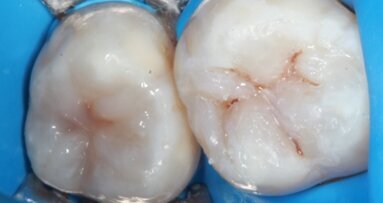

Po usunięciu zębów wykonano nacięcie na grzbiecie wyrostka zębodołowego, odwarstwiono pełny płat, oczyszczono dokładnie zębodoły i wyrównano brzeg kości. Założono 2 implanty pionowo w obszarze przednim i 2 dystalne pod kątem, ze stabilnością początkową umożliwiającą obciążenie natychmiastowe. Dobrane zostały i przykręcone do implantów odpowiednie łączniki niskoprolowe (Low Profile Abutments). Następnie przymocowano cylindry tymczasowe i wcześniej przygotowane ruchome protezy przerobiono na prowizoryczne stałe mosty.